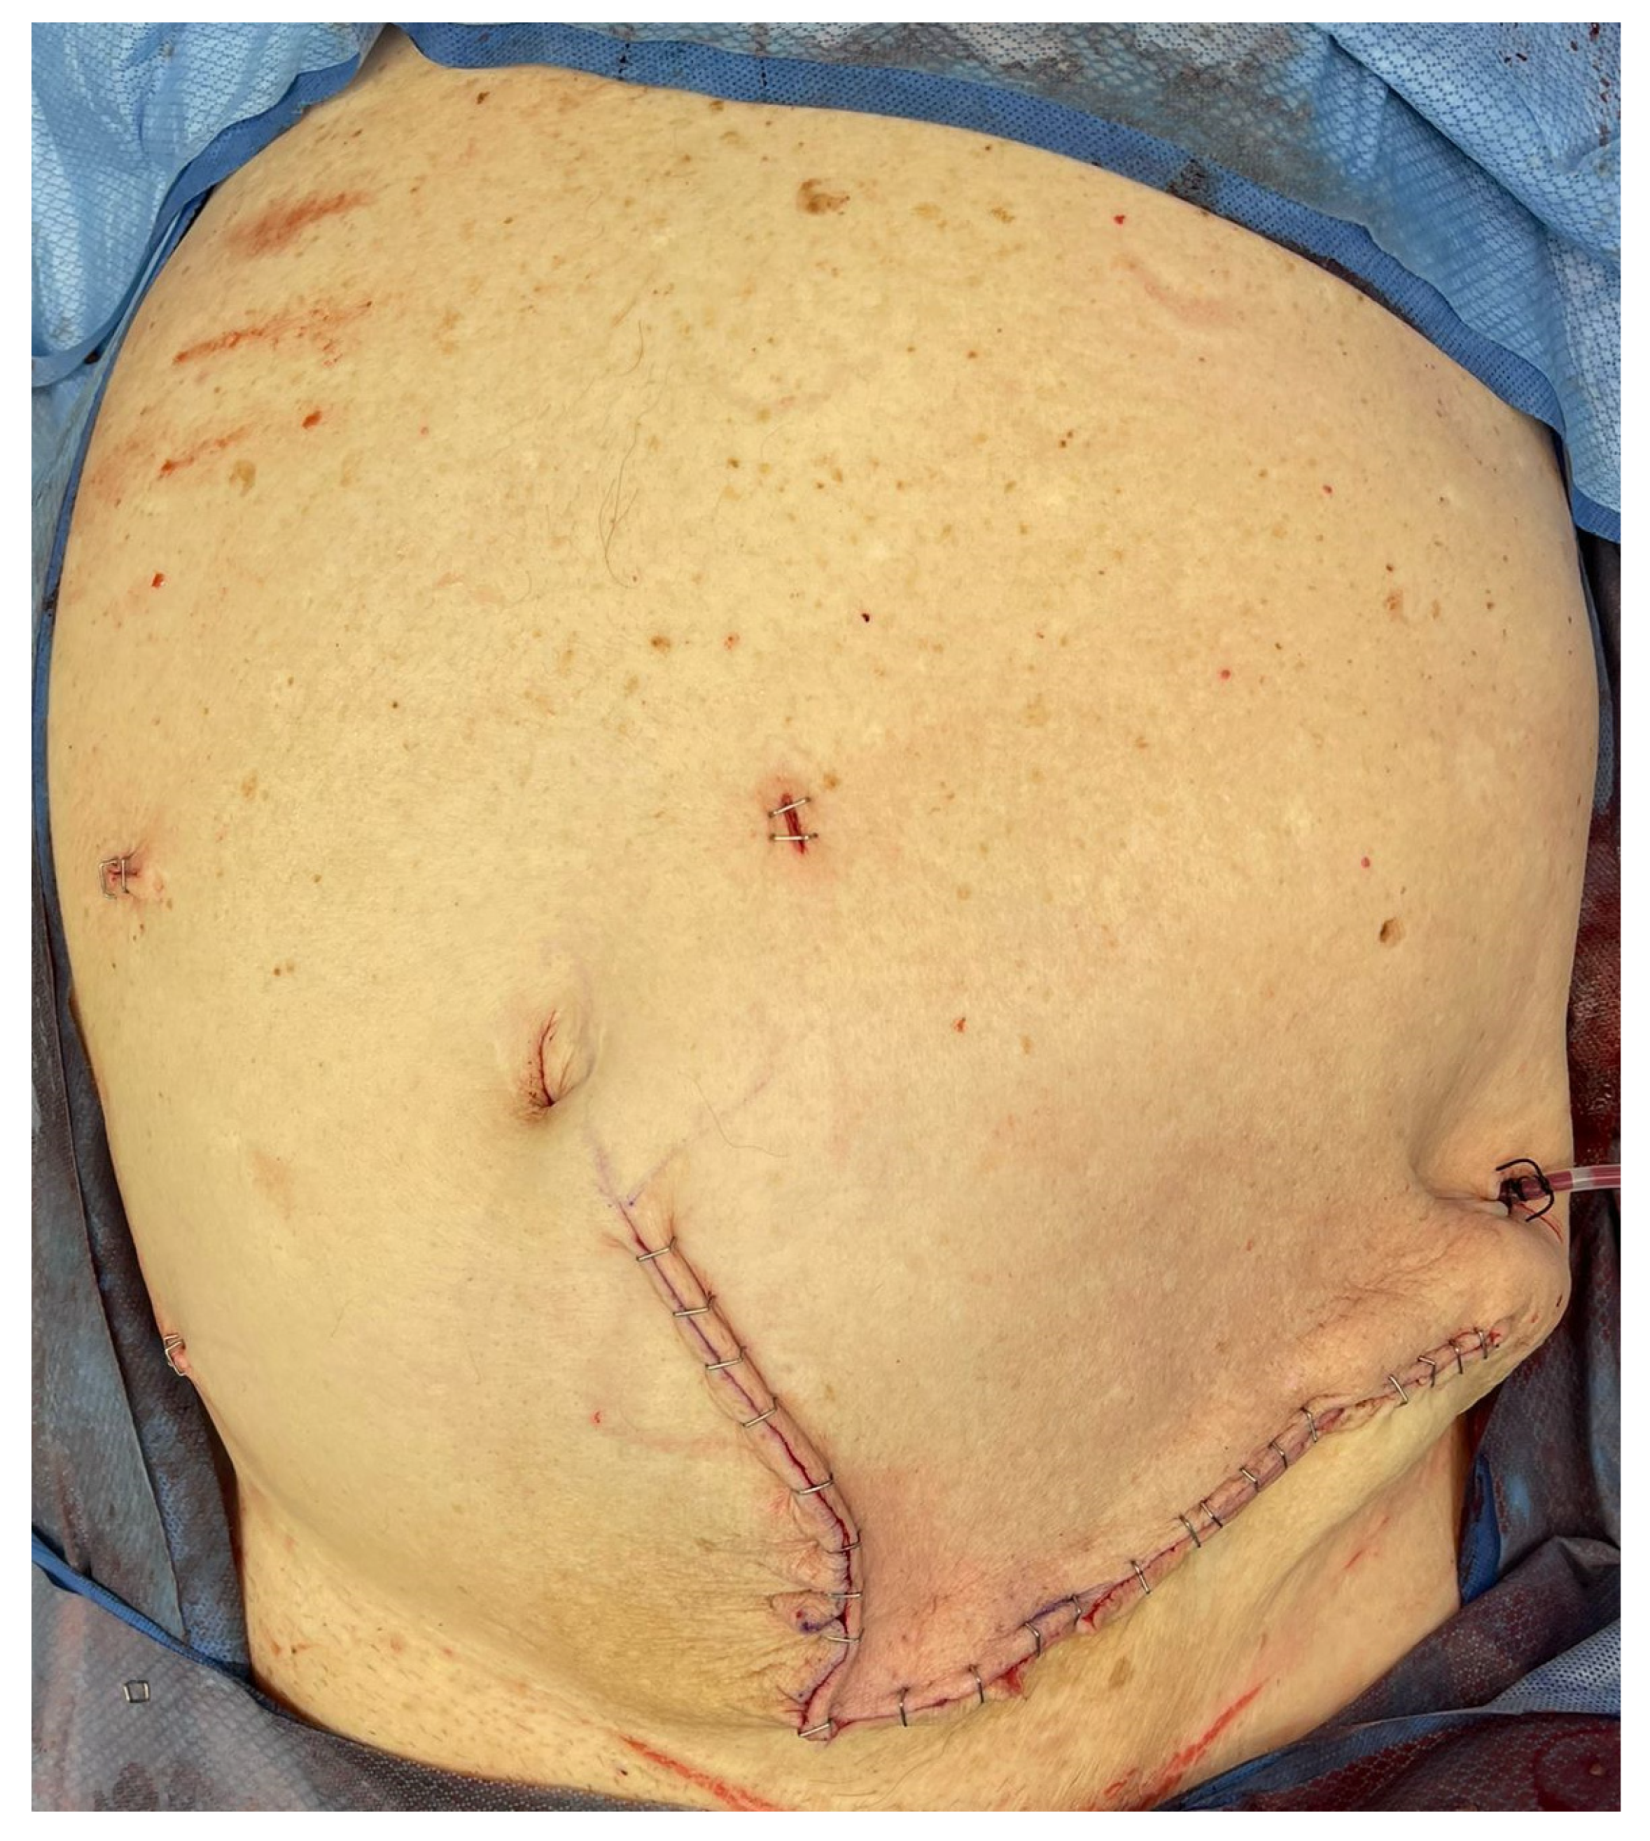

Figure 3.

Clinical photograph of the external appearance of the hernial sac with attenuated overlying skin.